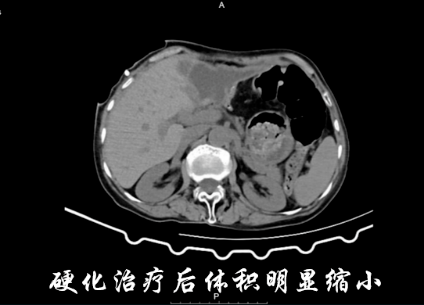

为彻底破坏囊肿囊壁,防止复发,团队并未急于求成,而是根据囊腔大小和张奶奶的耐受情况,分阶段进行硬化治疗。10月14日,首次在超声引导下进行酒精与聚桂醇联合硬化治疗,张奶奶没有出现明显不适。第二天张敬强主任医师查房时,她高兴地说:“吃饭香了,也不怎么疼了。”

10月15日下午,团队再次为张奶奶进行硬化治疗。医护人员先用生理盐水冲洗囊腔,再依次用无水酒精、聚桂醇原液反复冲洗,直到囊液变得清亮。经过四次规范治疗后,引流液仅剩下约10ml,最终成功为张奶奶拔除了引流管。

治疗结束后,张奶奶的恢复速度超出了预期。不仅腹痛、腹胀的症状彻底消失,进食量也恢复到了患病前的水平。复查结果显示,穿刺点没有出现感染、出血等并发症,身体各项指标逐渐趋于稳定。